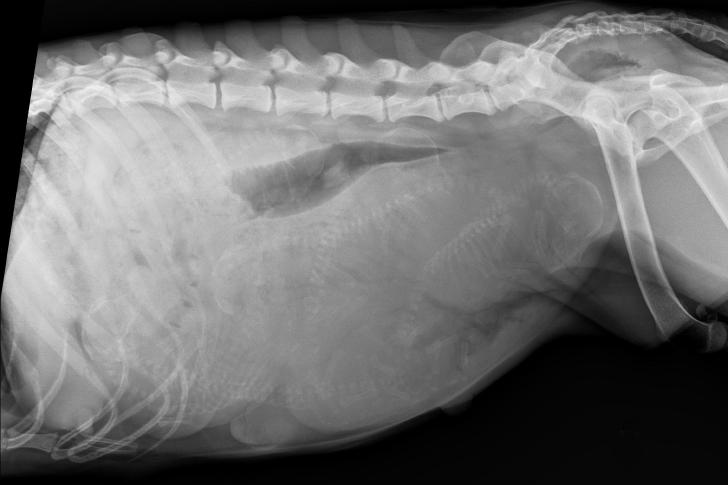

グリーンの手がローラを診察台に落ち着かせると、その熟練した視線は即座に腹部の顕著な膨らみに釘付けになった。画像診断では異例の多胎を示唆していたが、実際に目にしたことで彼は躊躇した。十匹?十一匹?それ以上かもしれない。標準を超えた数だが、可能性の範囲内ではあった。

グレースの表情——信じられないというように大きく見開かれた瞳——は何の説明も必要としなかった。彼女は控えめな数の子犬を想像していたのだ。はるかに大規模な準備を必要とするような数は想定外だった。グリーンは落ち着いた口調で、そのような多胎妊娠に必要なことを説明した:より密な監視、慎重なペース配分、そして忍耐。周囲ではスタッフが慣れた沈黙の中で動き、清潔なリネン、保温器具、医療用品を準備していた。場内の空気は変わり、全員が長期化し不確実な分娩に備え始めた。